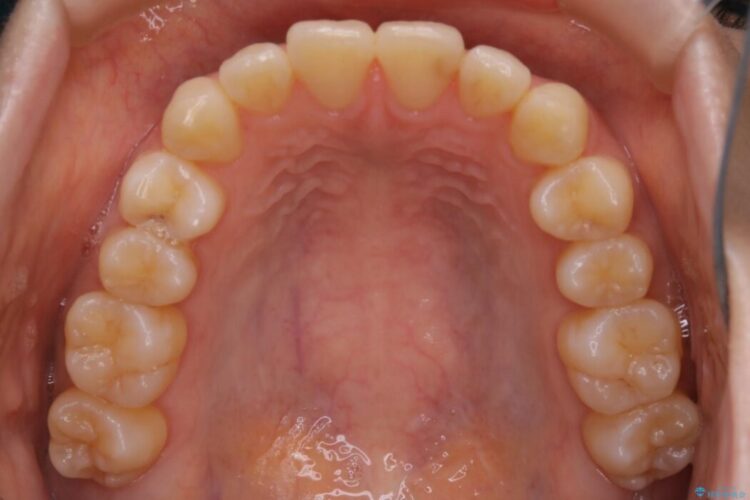

検査をしたところ奥歯の噛み合わせなどに問題が見られなかったため、軽度のねじれがある下顎前歯に焦点を当てた部分矯正の適応が可能と判断し、インビザラインのライトパッケージをご提案しました。

本症例では奥歯に関して問題がほぼ見られなかったため、部分矯正を行うことが可能と判断しました。